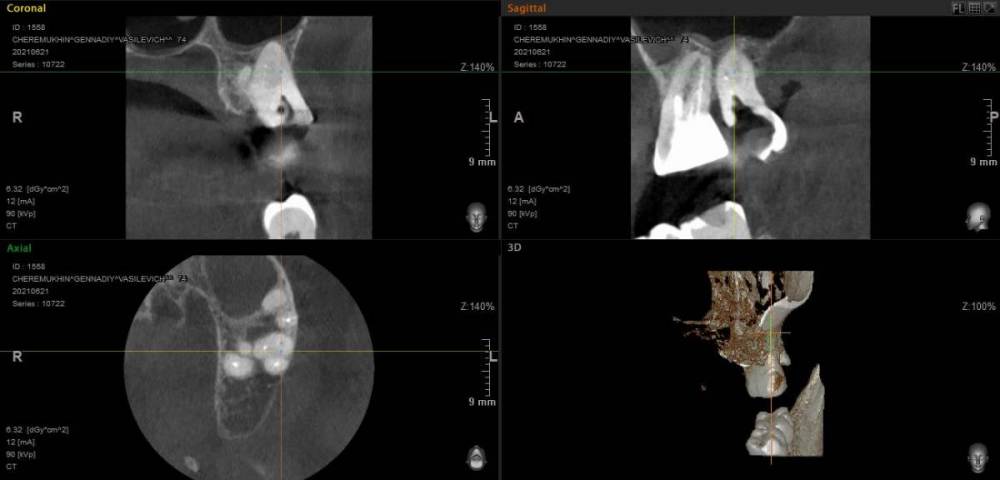

GENRY Опубликовано 6 сентября, 2021 Поделиться Опубликовано 6 сентября, 2021 Здравствуйте! Как лучше восстановить ( пусть частично) 28 зуб? Удаление не желательно т.к. с имплантацией связываться не хочу (синус лифтинг.. возраст 75 лет...) ,а опор для ортопедических конструкций нет. Кроме того боюсь, что в процессе удаления будет разрушена пломба 27 _го. Оптимизма добавляет история 27 го На орто 2012г показан 27 до его восстановления и до вмешательства в 28 зуб с добавлением в него пломбы в 2012г . Канал 28_го (небный ?) был уже запломбирован кем то раньше, скорее всего резорцин-формалиновой пастой) Доктор в 27 - м обнаружил на снимках 3 канала, наполовину прошел небный и полностью прошел дистально- щечный канал с наполнением их горячей гуттаперчей . Поскольку устье 3_го канала обнаружено не было, восстановил 27 зуб 2_мя стекловолоконными штифтами с использованием Build-It . Дистальную стенку сделал, кажется на основе пасты СПЕКТРУМ . К дальнейшей судьбе 27_го доктор отнесся скептически ( не более 2_х лет!), но похоже сработал надежно, пошел уже 10_й год, а 27 все стоит. Но 10 мес. назад выпала пломба 28 _го и он принял вид показанный на снимке. Не беспокоит. Хотелось бы повторить историю с 27_м, т.е. восстановить 28 по типу 27_го .... думаю мне хватит 5_7 лет... Регулировать нагрузки на этой стороне челюсти я научился. Сделал КТ сегмента 27_28 (В Пикассо, Vatech, просмотрщик EZ3D2009 plus ) но не смог найти ( сейчас живу в Феодосии ) терапевта работающего с этой программой. Кто то вообще не использует никакие КТ (но при этом берется за восстановление штифтом без перелечивания каналов) , кто то готов к перелечиванию, но полагается только на свои мануальные навыки, игнорируя КТ или формально глянув на пару проекций. На последней консультации добился 4-х снимков из КТ, но в общем то случайных и скорее всего не показательных.. Выкладываю скриншоты... Понял, что надо выходить за пределы городка и расширять собственное (к сожалению) понимание возможных вариантов лечения и их последствий. Вопросы по 28: 1. Если хотя бы один канал запломбирован (видимый на снимке) то это автоматически означает вскрытие камеры , а значит вскрытие и убитость содержимого (нервов, сосудов) всех остальных каналов , поскольку их устья на дне камеры? (Да, Нет, Другое) 2. Если Да, то нормально ли было пломбировать 28, не найдя и не залечив (с пломбировкой) другие каналы одновременно с небным (я имею ввиду сейчас самую раннюю пломбировку, до представленного орто) 3. Поскольку пломбировки всех каналов (сколько их ?) точно не было, то за эти 10-15 (?) лет (уже сейчас зуб стоит открытым почти год (ковид, консультации..)) должен развится пульпит, периодонтит... ? Или не обязательно? Ничего не болело, никаких выделений не было 4. Есть ли признаки какой либо хроники, воспалений в тканях на снимках? 5. Если ткани зуба и около него в порядке, то может не обязательно перелечивать все каналы, чтобы не ослаблять зуб? А только те, в которые будут вставлены штифты? Вкладка, похоже исключается т.к. феррул не замкнут на стыке с 27 зубом. 6. Есть ли какие либо оценки минимального количества требуемых штифтов ? 7 . Поскольку за 4 консультации я так и не получил ответов и снимков срезов (по КТ )показывающих количество и топологию корней и каналов, то придется добывать эту информацию самому. Буду благодарен за ссылки на материалы показывающих как это делается т.е. в каких из 3 проекций, при каком положении осей и.т.п. Я нашел только хороший ролик Ервандяна А.Г., но мне недостаточно, не хватает знания топологии зубов. Спасибо за внимание. Ссылка на комментарий